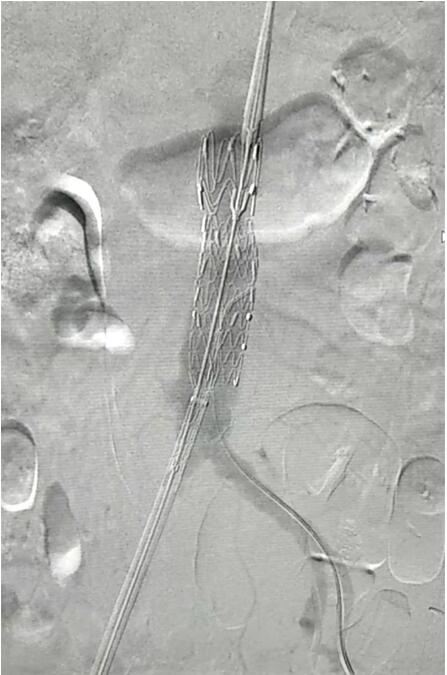

血管介入科行腹主動(dòng)脈瘤覆膜支架隔絕術(shù)(“褲衩”支架植入)。圖1